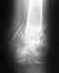

на 7 месяце беременности появились сильные боли в правом суставе и затем храмота по нарастающей,прокесарили экстренно на 37 неделе,спинальная анестезия.Появилась острая боль в тазобедренном суставе. отдаёт по всей ноге, ходить невозможно.Провели КТ,МРТ - врождённая дисплазия, вывернуто подвздошно - крестцовое сочленение,защемление нерва.Проведённое лечение результатов не даёт.Пожалуйсто посоветуйте что делать. Мне 40 лет,врач КДЛ,3 роды, хромота с тупой болью периодически появлялась в последние 8 лет.